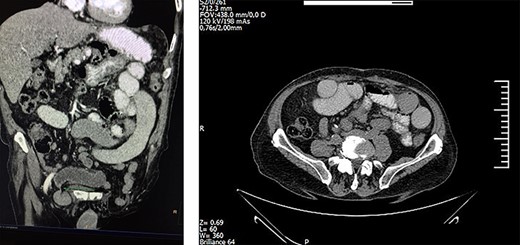

Laboratory examination revealed increased levels of C-reactive protein, LDH and neutrophils. Subsequent computed tomography (CT) and magnetic resonance imaging (MRI) of the abdomen and the pelvis indicated bowel obstruction of the sigmoid colon and obstruction of several loops of the small intestine as well (Fig 1). Herein, the patient underwent emergency laparotomy 2 h after he was initially assessed by the surgical team.